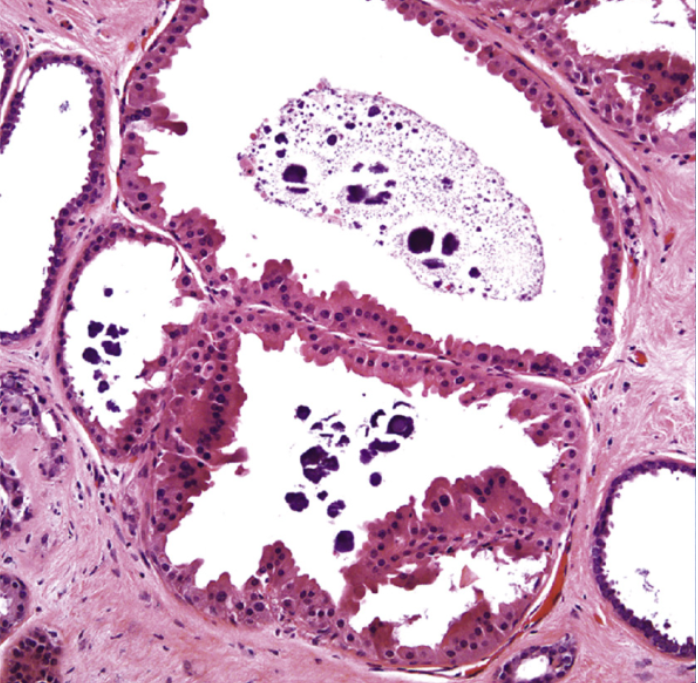

What pathology is indicated here?

fibrocystic changes

Note the bluish hue to the conglomerates in the cyst